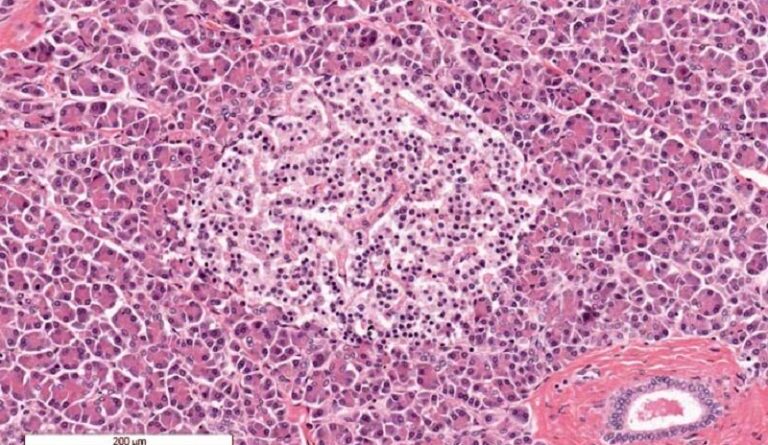

Estas investigaciones son parte de un grupo limitado de ensayos innovadores que emplean células madre para tratar la diabetes, una enfermedad que afecta a cerca de 500 millones de personas en todo el mundo. La mayoría de los afectados sufren diabetes tipo 2, en la que el cuerpo no produce suficiente insulina o presenta dificultades para utilizar la hormona de manera efectiva. Por otro lado, en la diabetes tipo 1, el sistema inmunitario ataca las células de los islotes del páncreas.

Los trasplantes de islotes pueden ser una opción de tratamiento para la enfermedad, pero la escasez de donantes es un importante desafío. Además, los receptores deben someterse a un tratamiento con medicamentos inmunosupresores para prevenir el rechazo del tejido trasplantado. Las células madre tienen la capacidad de generar cualquier tipo de tejido del cuerpo y se pueden cultivar indefinidamente en laboratorio, lo que sugiere que podrían proporcionar una fuente ilimitada de tejido pancreático. Al utilizar tejido creado a partir de las propias células del paciente, los investigadores esperan, además, eliminar la necesidad de inmunosupresores.

En este estudio informan sobre los resultados de un año de un paciente como análisis preliminar de un primer ensayo clínico en humanos de fase I que evalúa la viabilidad del trasplante autólogo de islotes derivados de células madre pluripotentes inducidas químicamente (islotes CiPSC) debajo de la vaina del recto anterior abdominal para el tratamiento de la diabetes tipo 1.